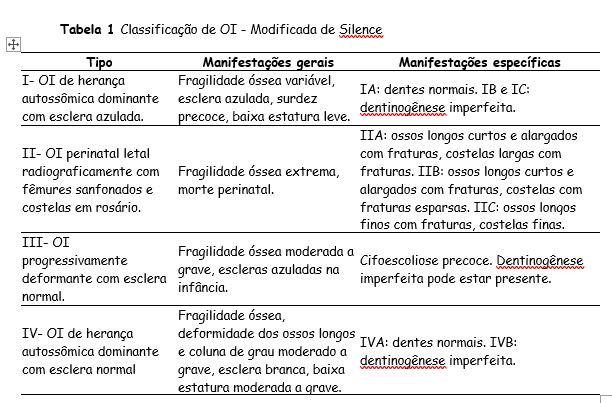

Devido à variabilidade fenotípica considerável, Sillence et al desenvolveram uma classificação dos subtipos OI baseada em características clínicas e gravidade da doença (Tabela 1): OI tipo I, forma leve, comum, com escleras azuladas; OI tipo II, forma perinatal letal; OI tipo III, forma grave e progressivamente deformante, com esclera normal; e OI tipo IV, forma de gravidade moderada, com esclera normal. A classificação de Sillence vem sendo repetidamente revista em momentos de identificação de novos genes causadores da OI. (VALADARES et al., 2014).